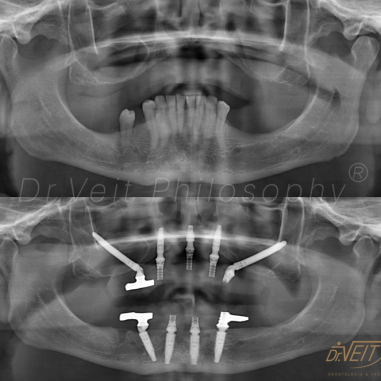

Arte de reabilitar os casos “impossíveis”. Pacientes que buscam a reabilitação oral podem conquistar um belo sorriso com segurança, mais conforto e tranquilidade com o uso do Implante Zigomático. A técnica possui o diferencial de realizar a implantação no osso zigomático e é indicada para casos de perda óssea maxilar avançada.